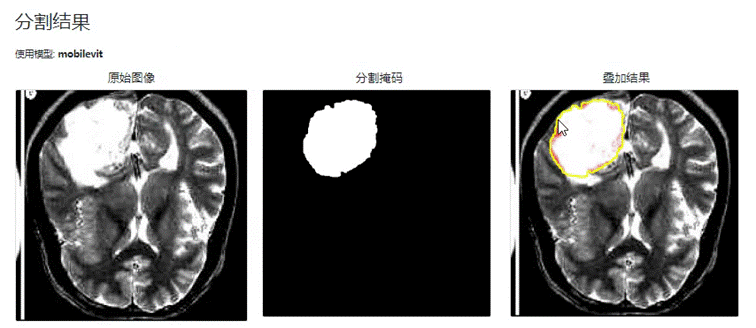

在相同的实验环境和参数设置下,对TransUNet 和 MobileViT 算法两种模型在医学图像分割任务中进行了对比实验。实验结果如下图所示:

图 4-1 TransUNet模型分割结果

图 4-2 MobileViT模型分割结果